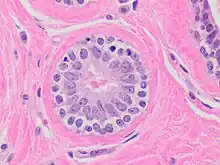

Acinus

De façon générale le terme acinus (du latin acinus, grain de raisin ; au pluriel acini ou acinus) désigne une cavité épithéliale arrondie bordée par des cellules sécrétrices qui débouche dans le canal excréteur d'une glande.

Acini séreux

• Cellule de forme pyramidale

• Lumière étroite

• noyau central arrondi

• Réticulum endoplasmique rugueux (RER) ou granuleux (REG) très développé, cytoplasme souvent basophile

• Présence de grain de sécrétion au pôle apical. Rejette son produit de sécrétion selon un mode mérocrine.

Exemple : acinus pancréatique